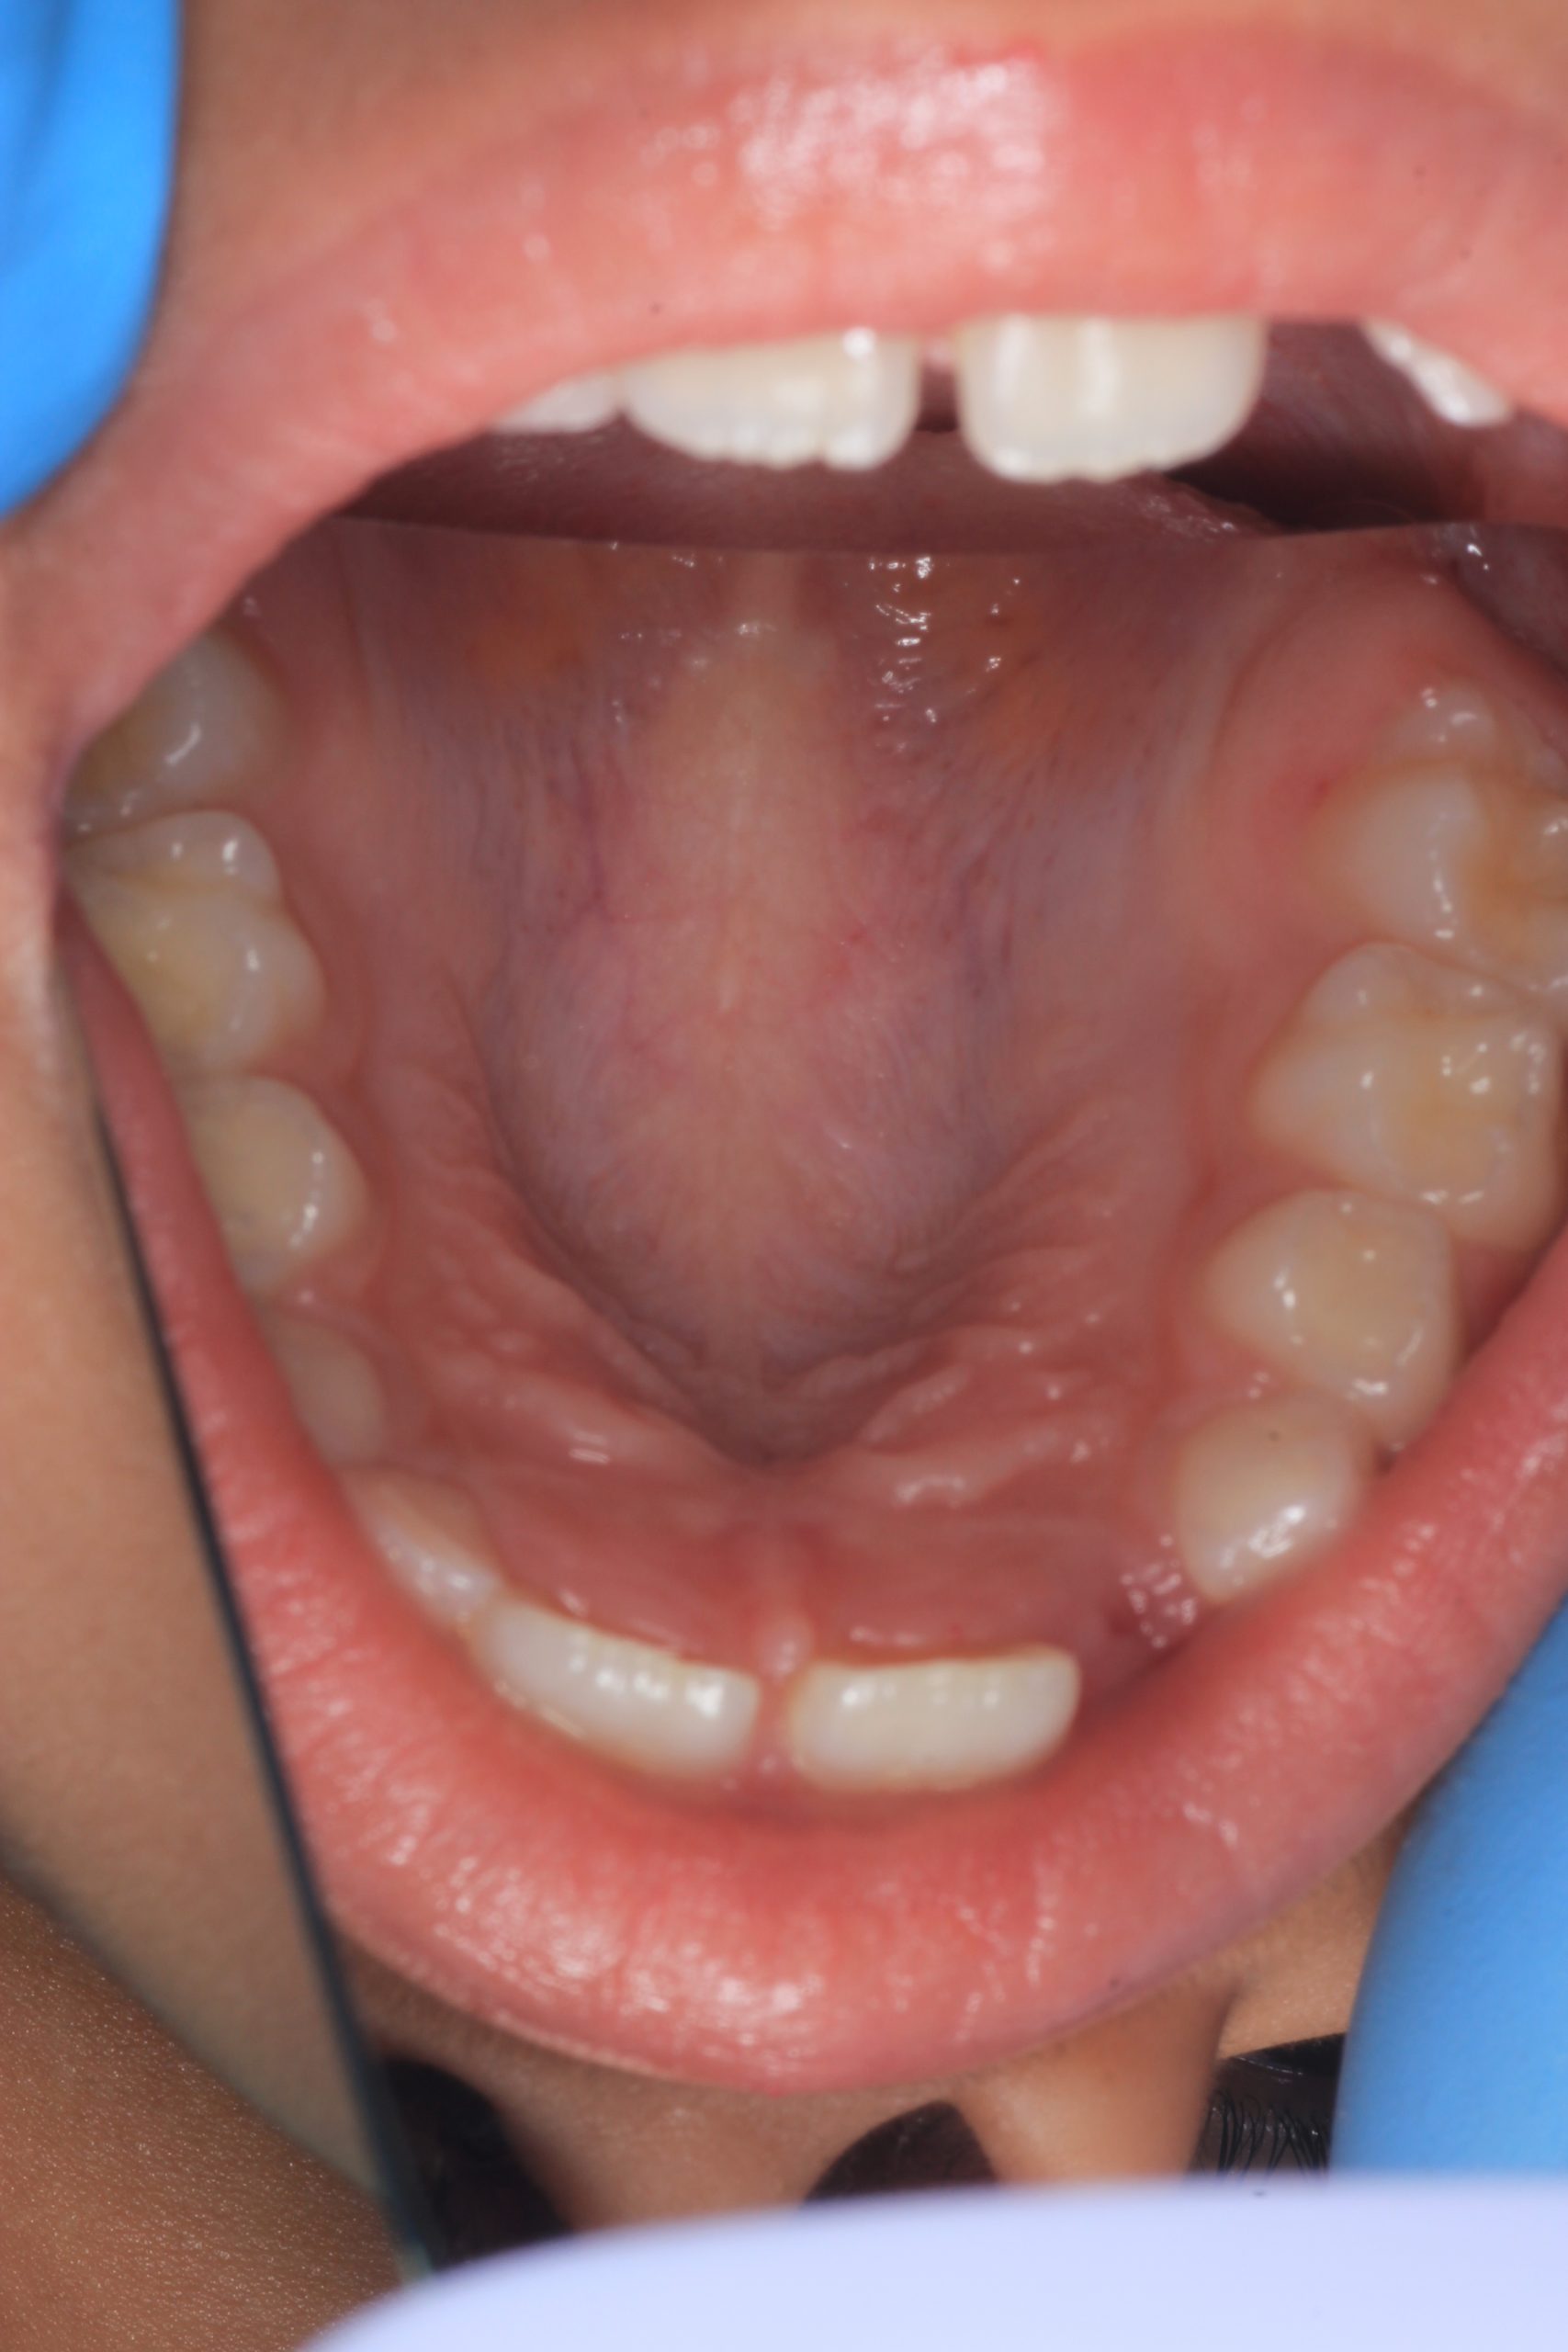

We examine the condition of teeth, gums, and bite. - Plaque Disclosure with Special Indicators

Areas that weren’t cleaned well appear purple. The darker the shade, the older the plaque. This helps both kids and parents understand where brushing needs to improve. - Brushing Training & Home Care Tools Selection